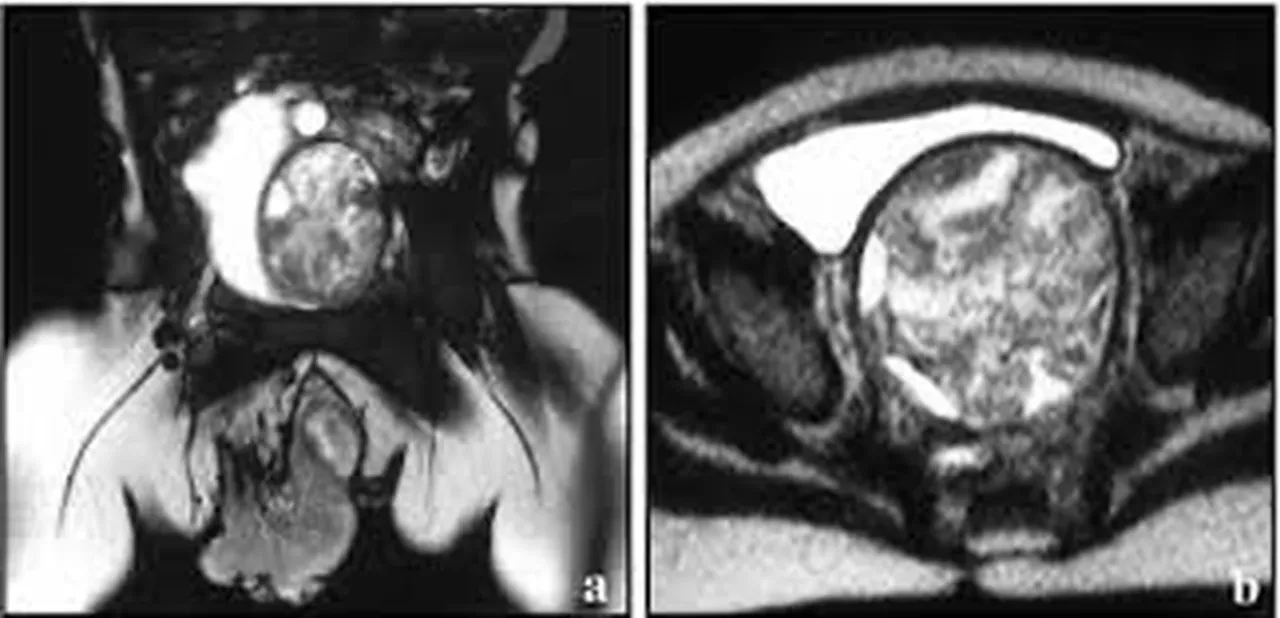

Rabdomyosarkom, kas veya fibröz dokuda gelişen nadir ve agresif bir yumuşak doku kanseridir. En sık 5-9 yaş arası çocuklarda görülür. Uzmanlar, ebeveynlerin çocuklarında fark ettikleri şişlikleri, açıklanamayan yorgunlukları ve mide rahatsızlıklarını ciddiye alması gerektiği konusunda uyarıyor.

Rabdomyosarkom, çocukluk çağında görülen yumuşak doku sarkomlarının en yaygın türüdür.

Erken teşhis edilmediğinde hızla yayılabilir.

Karında görüldüğünde, solunum güçlüğüne kadar ilerleyebilen bası semptomlarına neden olabilir.